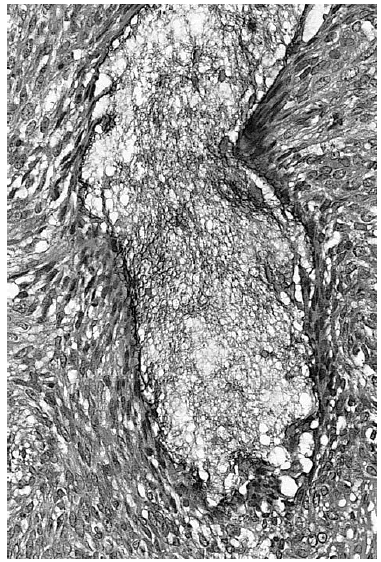

En dos biopsias previas sólo pudo apreciarse una epidermis psoriasiforme y un inflitrado linfocitario de predominio perifolicular, hallazgos que se consideraron compatibles con rosácea. Se instauraron tratamientos con metronidazol, tópico y oral, y con tetraciclinas orales, sin que se observara ninguna mejoría. En una tercera biopsia se encontaron hallazgos similares, pero con áreas de degeneración mucinosa a nivel de los folículos polisebáceos (figs. 2 y 3). Las tinciones de hierro coloidal y azul Alcián (pH 2,5) confirmaron la presencia de mucina a nivel folicular. El infiltrado seguía siendo foliculotrópico, sin atipias nucleares en los linfocitos ni epidermotropismo. Considerando estos hallazgos histológicos, la ausencia de otras dermatosis, la exclusión de procesos linfoproliferativos sistémicos y la evolución de la lesión se estableció el diagnóstico de mucinosis folicular primaria. La lesión fue tratada con PUVA (psoraleno y luz ultravioleta) con escasa mejoría.

Fig. 2.--Epidermis normal con infiltrados linfocitarios perifoliculares y áreas claras a nivel de los folículos pilosos.